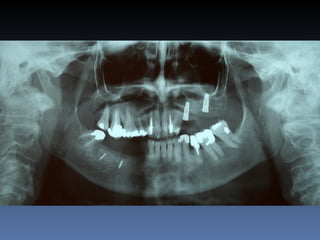

Silvana Ferraz Caetano

Idade – 53 anos

Sexo – Feminino

Raça – Caucasiana

ASA – II

Data- 26-04-2012

Diagnóstico:Desdentada parcial-maxila

Plano de tratamento:          Reabilitação das áreas

desdentadas com instalação de 6 implantes endo-

ósseos para reabilitação protética fixa.

Área posterior enxertada com

Aloenxerto Fresco-congelado